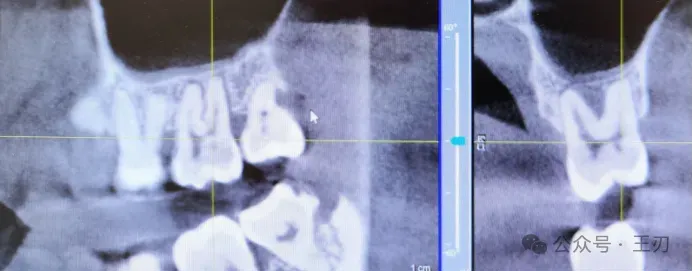

同样的,17的远中根据探诊结果有牙周深袋,将视图拉到舌侧(上图),可以看到17远中有明显的骨吸收,而将视图拉到颊侧(下图),看不到明显骨吸收。

27的远中同样有探诊深袋,将视图拉到舌侧(上图),可以看到骨吸收,拉到颊侧(下图),看不到明显骨吸收。